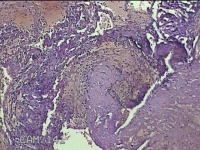

左侧卵巢黄体

性别

女

年龄

34岁

临床诊断

左侧卵巢黄体破裂

一般病史

下腹疼痛11小时。

标本名称

大体所见

灰白暗红色囊壁样组织3x2.3x0.3cm一堆,表面光滑,内壁高低不平,切面灰白暗红色,囊壁厚约0.1cm。

黄体囊肿?

有可能,所提供图片不具有诊断价值。